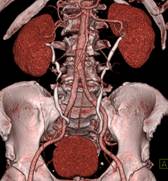

※肝脏、胰腺、肾脏CT-DSA 及灌注功能一站式检查

脑血管畸形CTA ,大血管成像:动态容积成像实现大范围动态血管检查